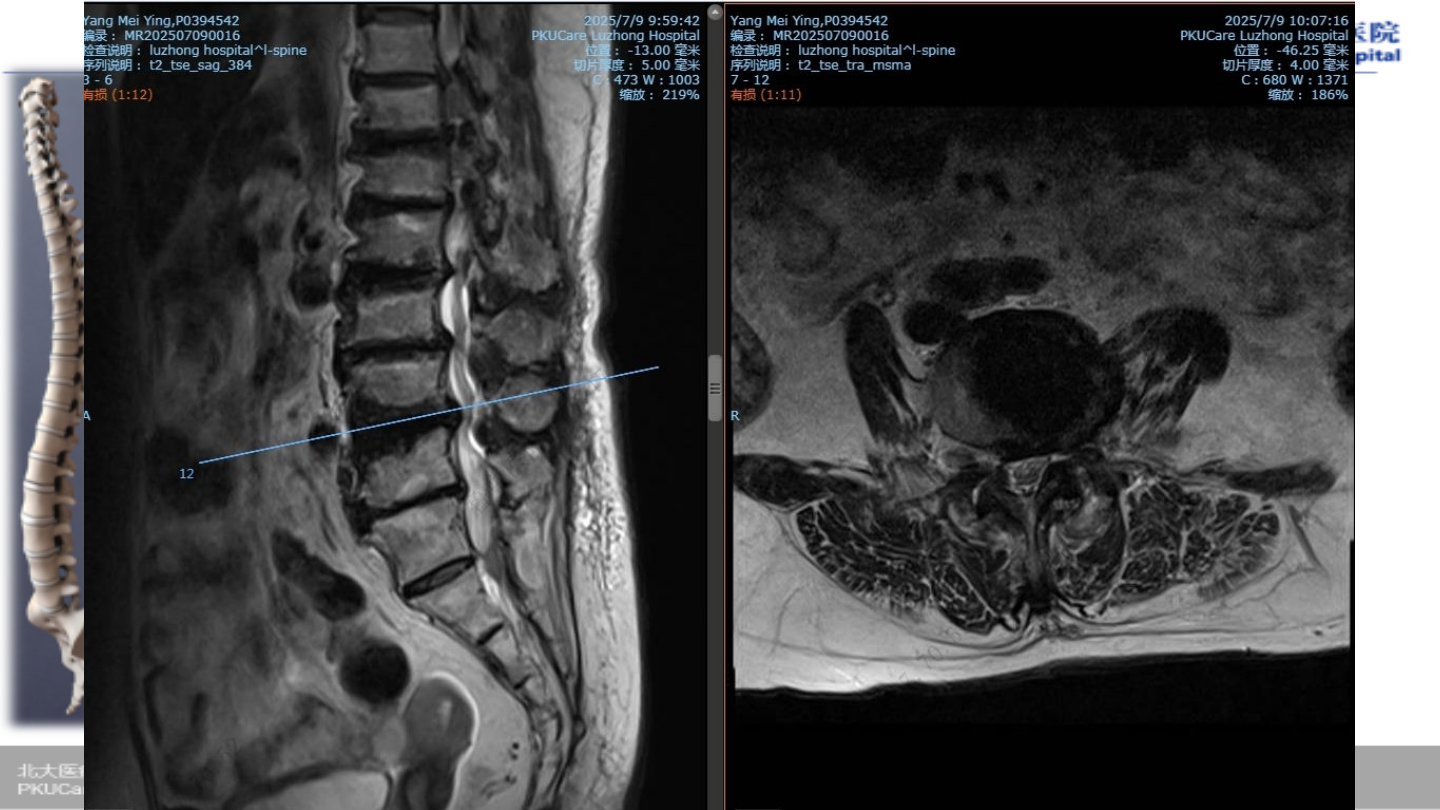

术前

MRI